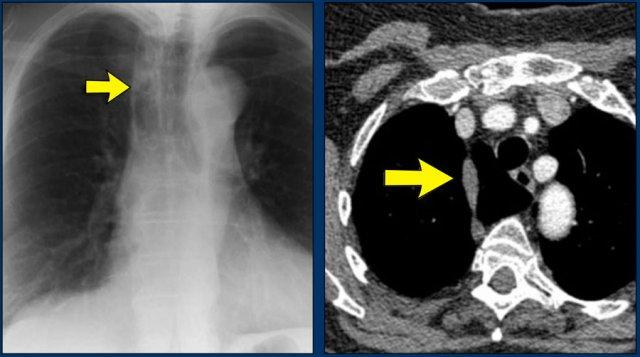

Dịch chuyển đường azygô-thực quản (1) – Thoát vị hoành

Thoát vị hoành (đầu mũi tên) là nguyên nhân phổ biến nhất gây dịch chuyển đường azygô-thực quản quan sát thấy trên phim tư thế thẳng (PA).

Lưu ý hình ảnh khí trong túi thoát vị trên phim tư thế nghiêng (mũi tên đen).